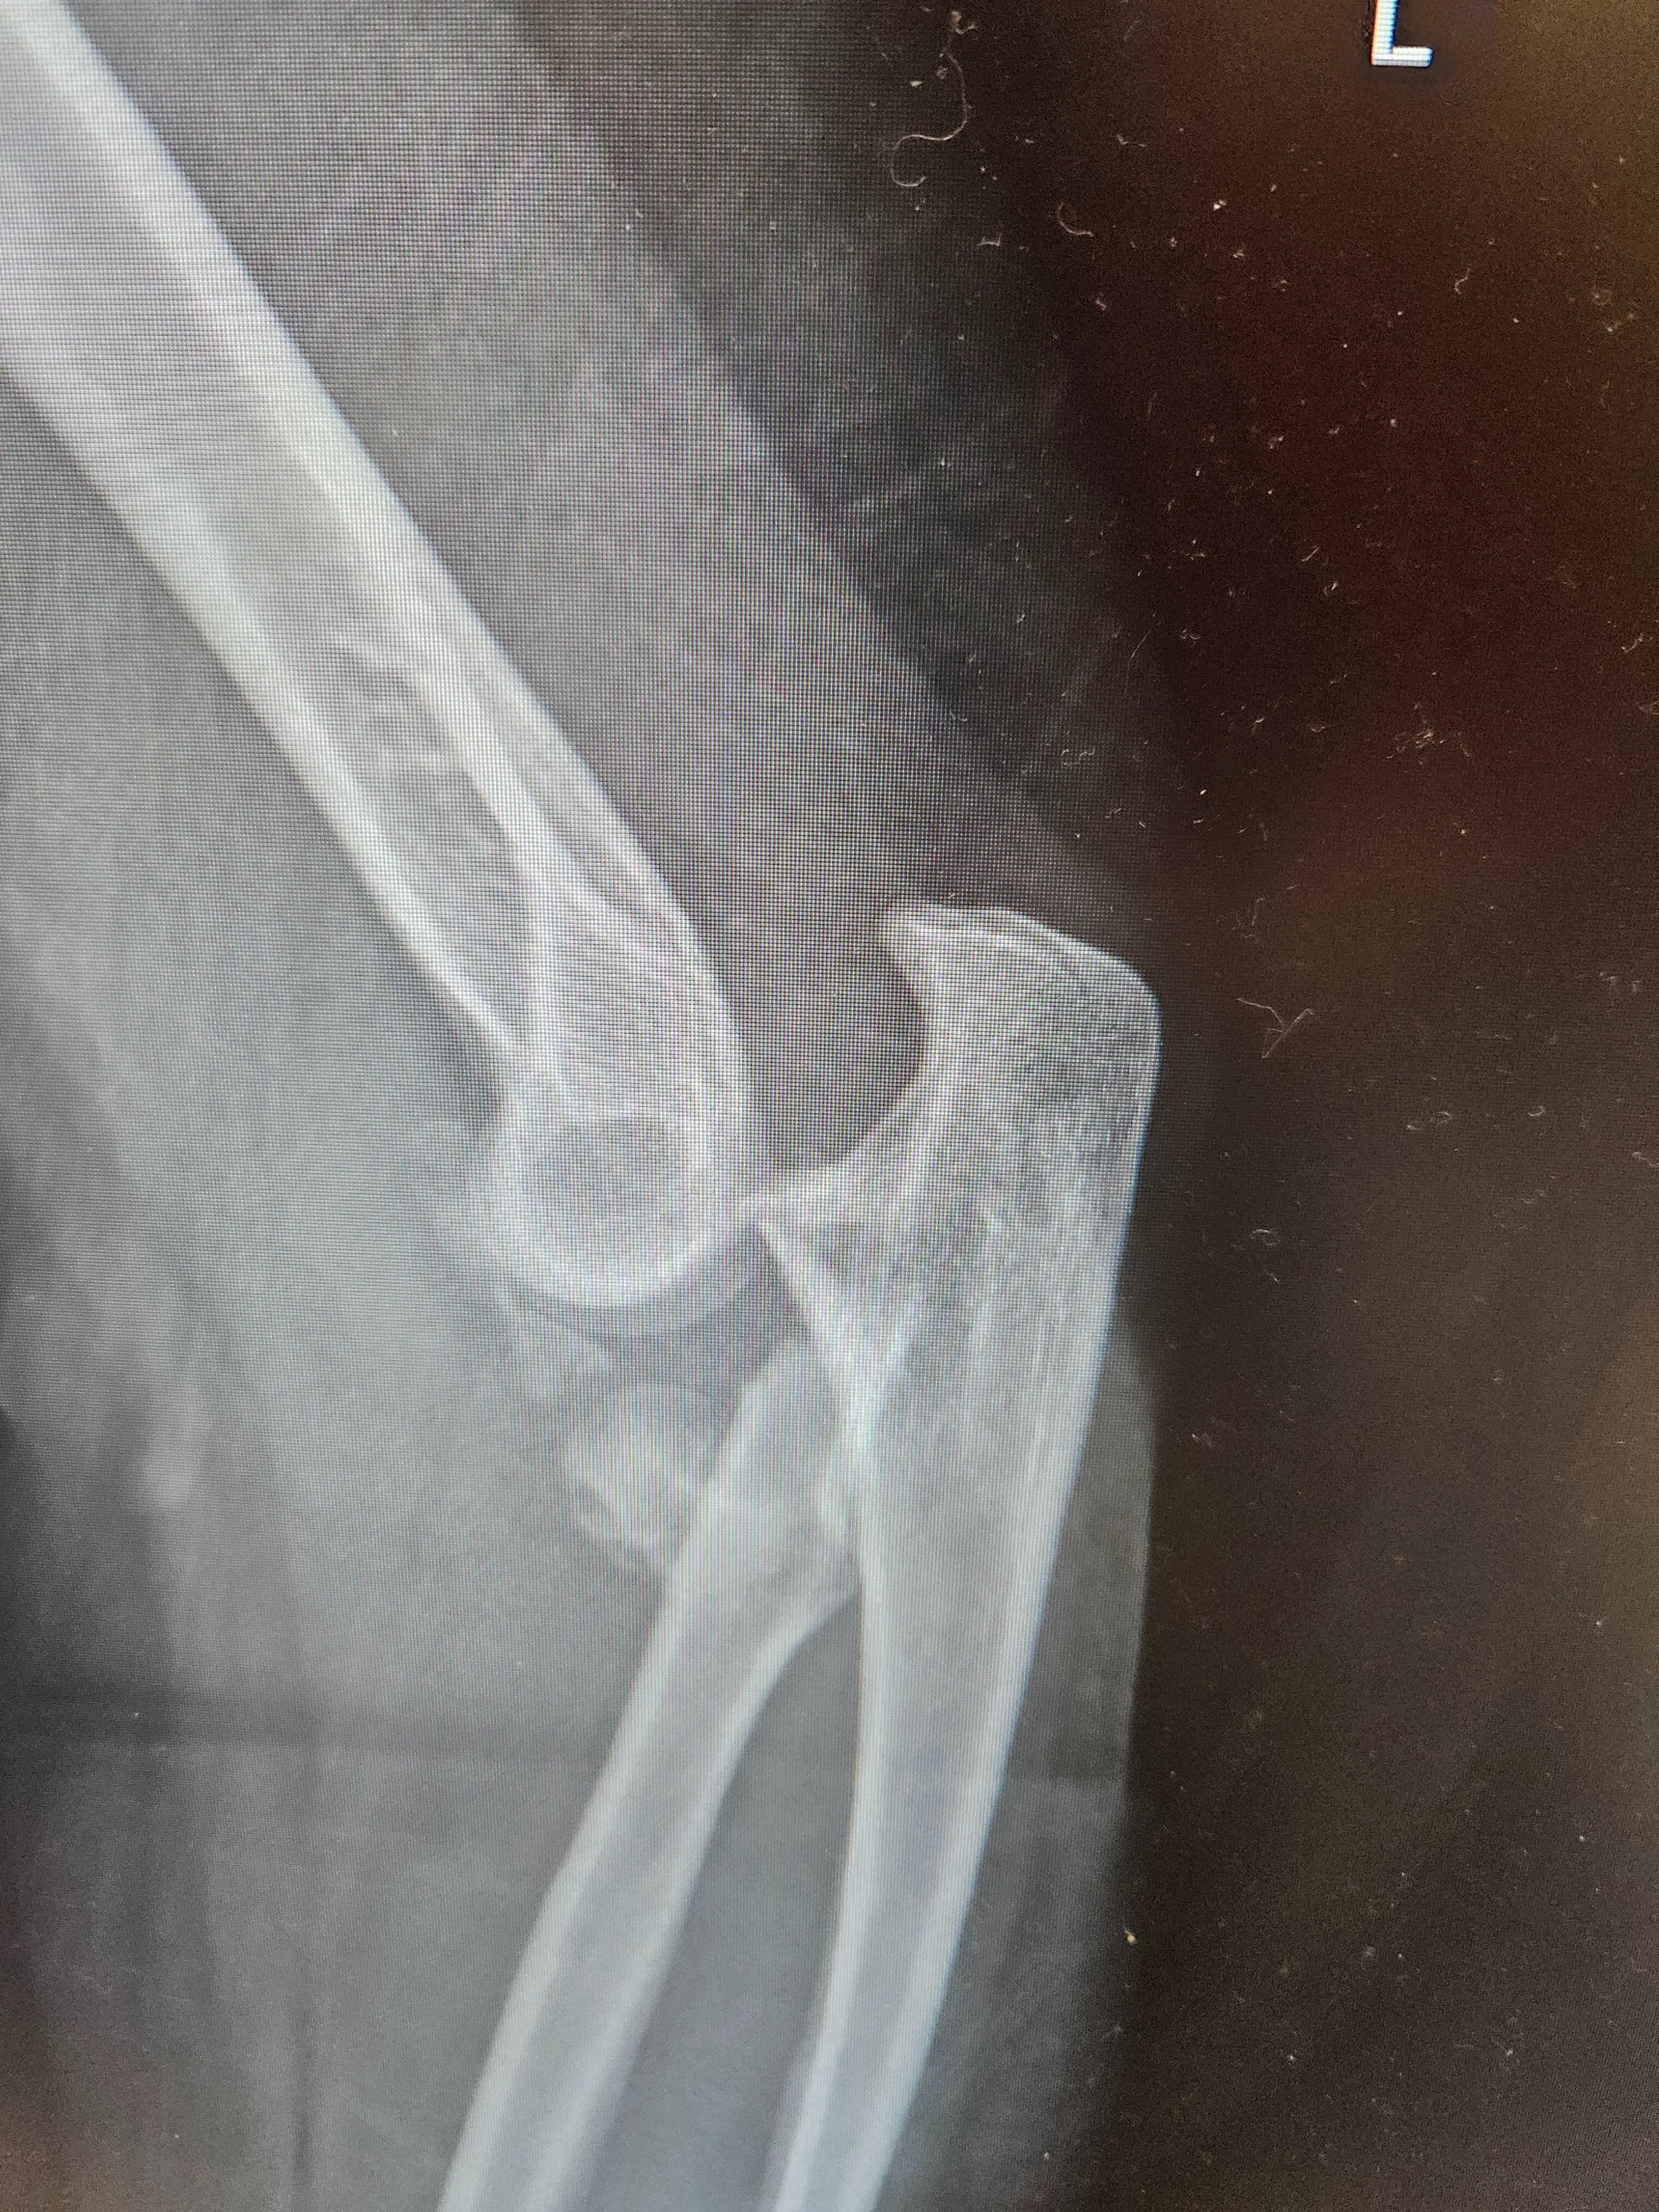

We’re raising funds to support our coworker and friend who recently suffered a serious fall, resulting in dislocated and fractured elbows on both arms. This unexpected injury has left her unable to work for the foreseeable future as she undergoes treatment and recovery.